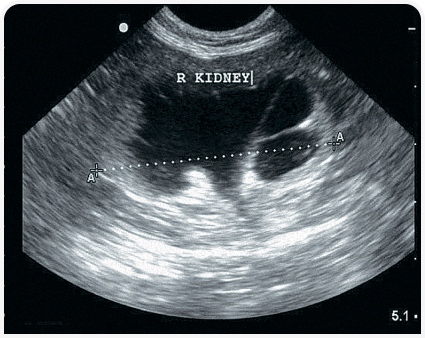

Что показывает УЗИ брюшной полости

Во время УЗИ можно обнаружить изменения в форме, размерах, плотности тканей. Комплексное обследование позволяет оценить работу всех важных органов ЖКТ — 12-перстной кишки, желудка, поджелудочной железы, почек, печени, желчного пузыря, селезенки, репродуктивных органов. Объем исследования зависит от показаний и состояния животного.

Комплексная оценка органов брюшной полости

Пациент: Тиша, кошка, 7 лет

Жалобы: Снижение аппетита, потеря веса за 3 недели. Активность снизилась, но без явной боли.

Диагноз: Умеренная гиперэхогенность печени (подозрение на жировую инфильтрацию), увеличение подчелюстных лимфоузлов. Желудок и кишечник без патологий.

Что дало УЗИ: УЗИ позволило быстро оценить состояние всех ключевых органов, выявить первопричину — нарушение обмена веществ. Направлено на дальнейшее обследование (анализы, диета) и исключены опухоли и обструкции.

Результат: Назначена гепатопротективная терапия и специализированный корм. Через месяц — нормализация аппетита, прибавка в весе, снижение ферментов.